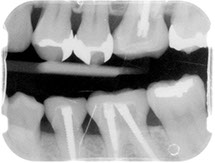

Before/After Photos